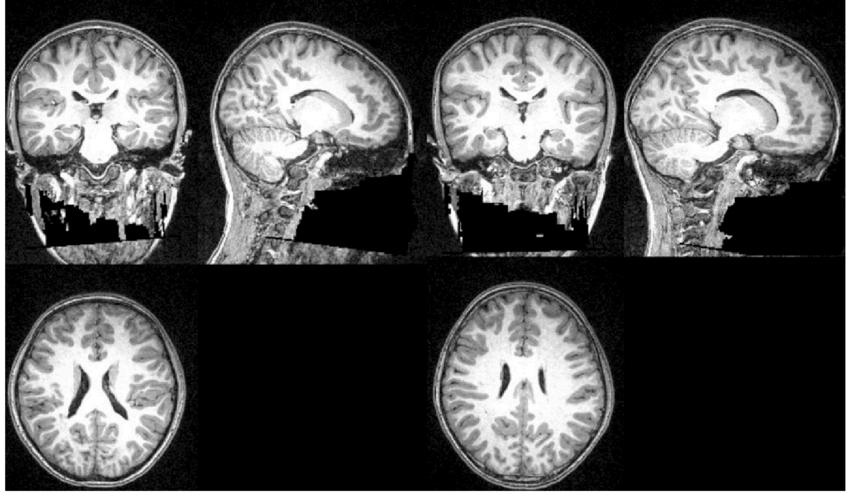

The usage of neuroplasticity is prevalent in the medical industry nowadays; it is used in stroke rehabilitation, mitigating neurodegenerative diseases, and in mental health treatment After a stroke–a loss of blood flow to part of the brain which damages one ’ s brain tissue–consistent longterm care is required for the patient’s swift recovery. Neuroplasticity harnesses the patient’s recovery process According to Physiopedia, neuroplasticity aids stroke rehabilitation by allowing healthy brain portions to recover for damaged areas by developing novel functions through processes like inter-hemispheric lateralization, formation of new connections in cortical regions, and reorganization of cortical representational maps. Furthermore, these are instinctive processes that assist such significant spontaneous recovery. Utilizing positron emission tomography (PET) and functional magnetic resonance imaging (fMRI)I–noninvasive imaging techniques–also helps people discover the latent phenomena of neuroplasticity. Patients who are suffering from neurodegenerative diseases–diseases resulting from neuron loss, representatively Alzheimer's and Parkinson's disease–can ameliorate their conditions via utilizing neuroplasticity. In accordance with BMC, neuroplasticity helps Alzheimer's and Parkinson's patients by potentially enhancing the function of brains and decelerating the speed of the disease’s progression Currently, neurologists are working on developing brain stimulation techniques that aim to mobilize neuroplasticity’s ability for essentially executing treatment by using deep brain stimulation (DBS) and transcranial magnetic stimulation (TMS)–the specific regions of the brain. What is more, even mental health problems can be coped with neuroplasticity As stated by Life Stance Health, through intentional practices involving neuroplasticity, people can fortify positive thoughts and maneuvers while weakening negative ones. Specifically, people with depression problems can train their brains to wrestle with self-activated negative thoughts, and foster selflove. Furthermore, Cognitive Behavioral Therapy (CBT) provides methods to reconstruct thought processing Also, regular exercise increases neuroplasticity and promotes cognitive function and mood regulation To sum up, neuroplasticity is widespread throughout diverse aspects of the medical system and deeply embedded into our lives. Aside from the particular pathways to strengthen people’s neuroplasticity, methods such as neurofeedback and brain-computer interfaces are also obliging to such processes.

In 2022, Doctor John Hutton carried out a study looking at MRI scans of developing children's brains and comparing the structure of those with relatively greater screen time to those with less exposure to screens. The main focus was on the cortical thickness (the brain’s outer layer) which is responsible for creativity and thinking, and the sulcal depth (the distance between the cortical and the hull). The study concluded that a greater screen time shows a smaller cortical thickness and sulcal depth which resulted in faster advancement in visual processing but slower and underdevelopment in areas requiring more complicated skills including language proficiency, reading and social interactions Doctor Hutton has stated that limiting a child’s screen time results in healthy development and capability to adjust to new environments (Cincinnati Children’s, 2022)